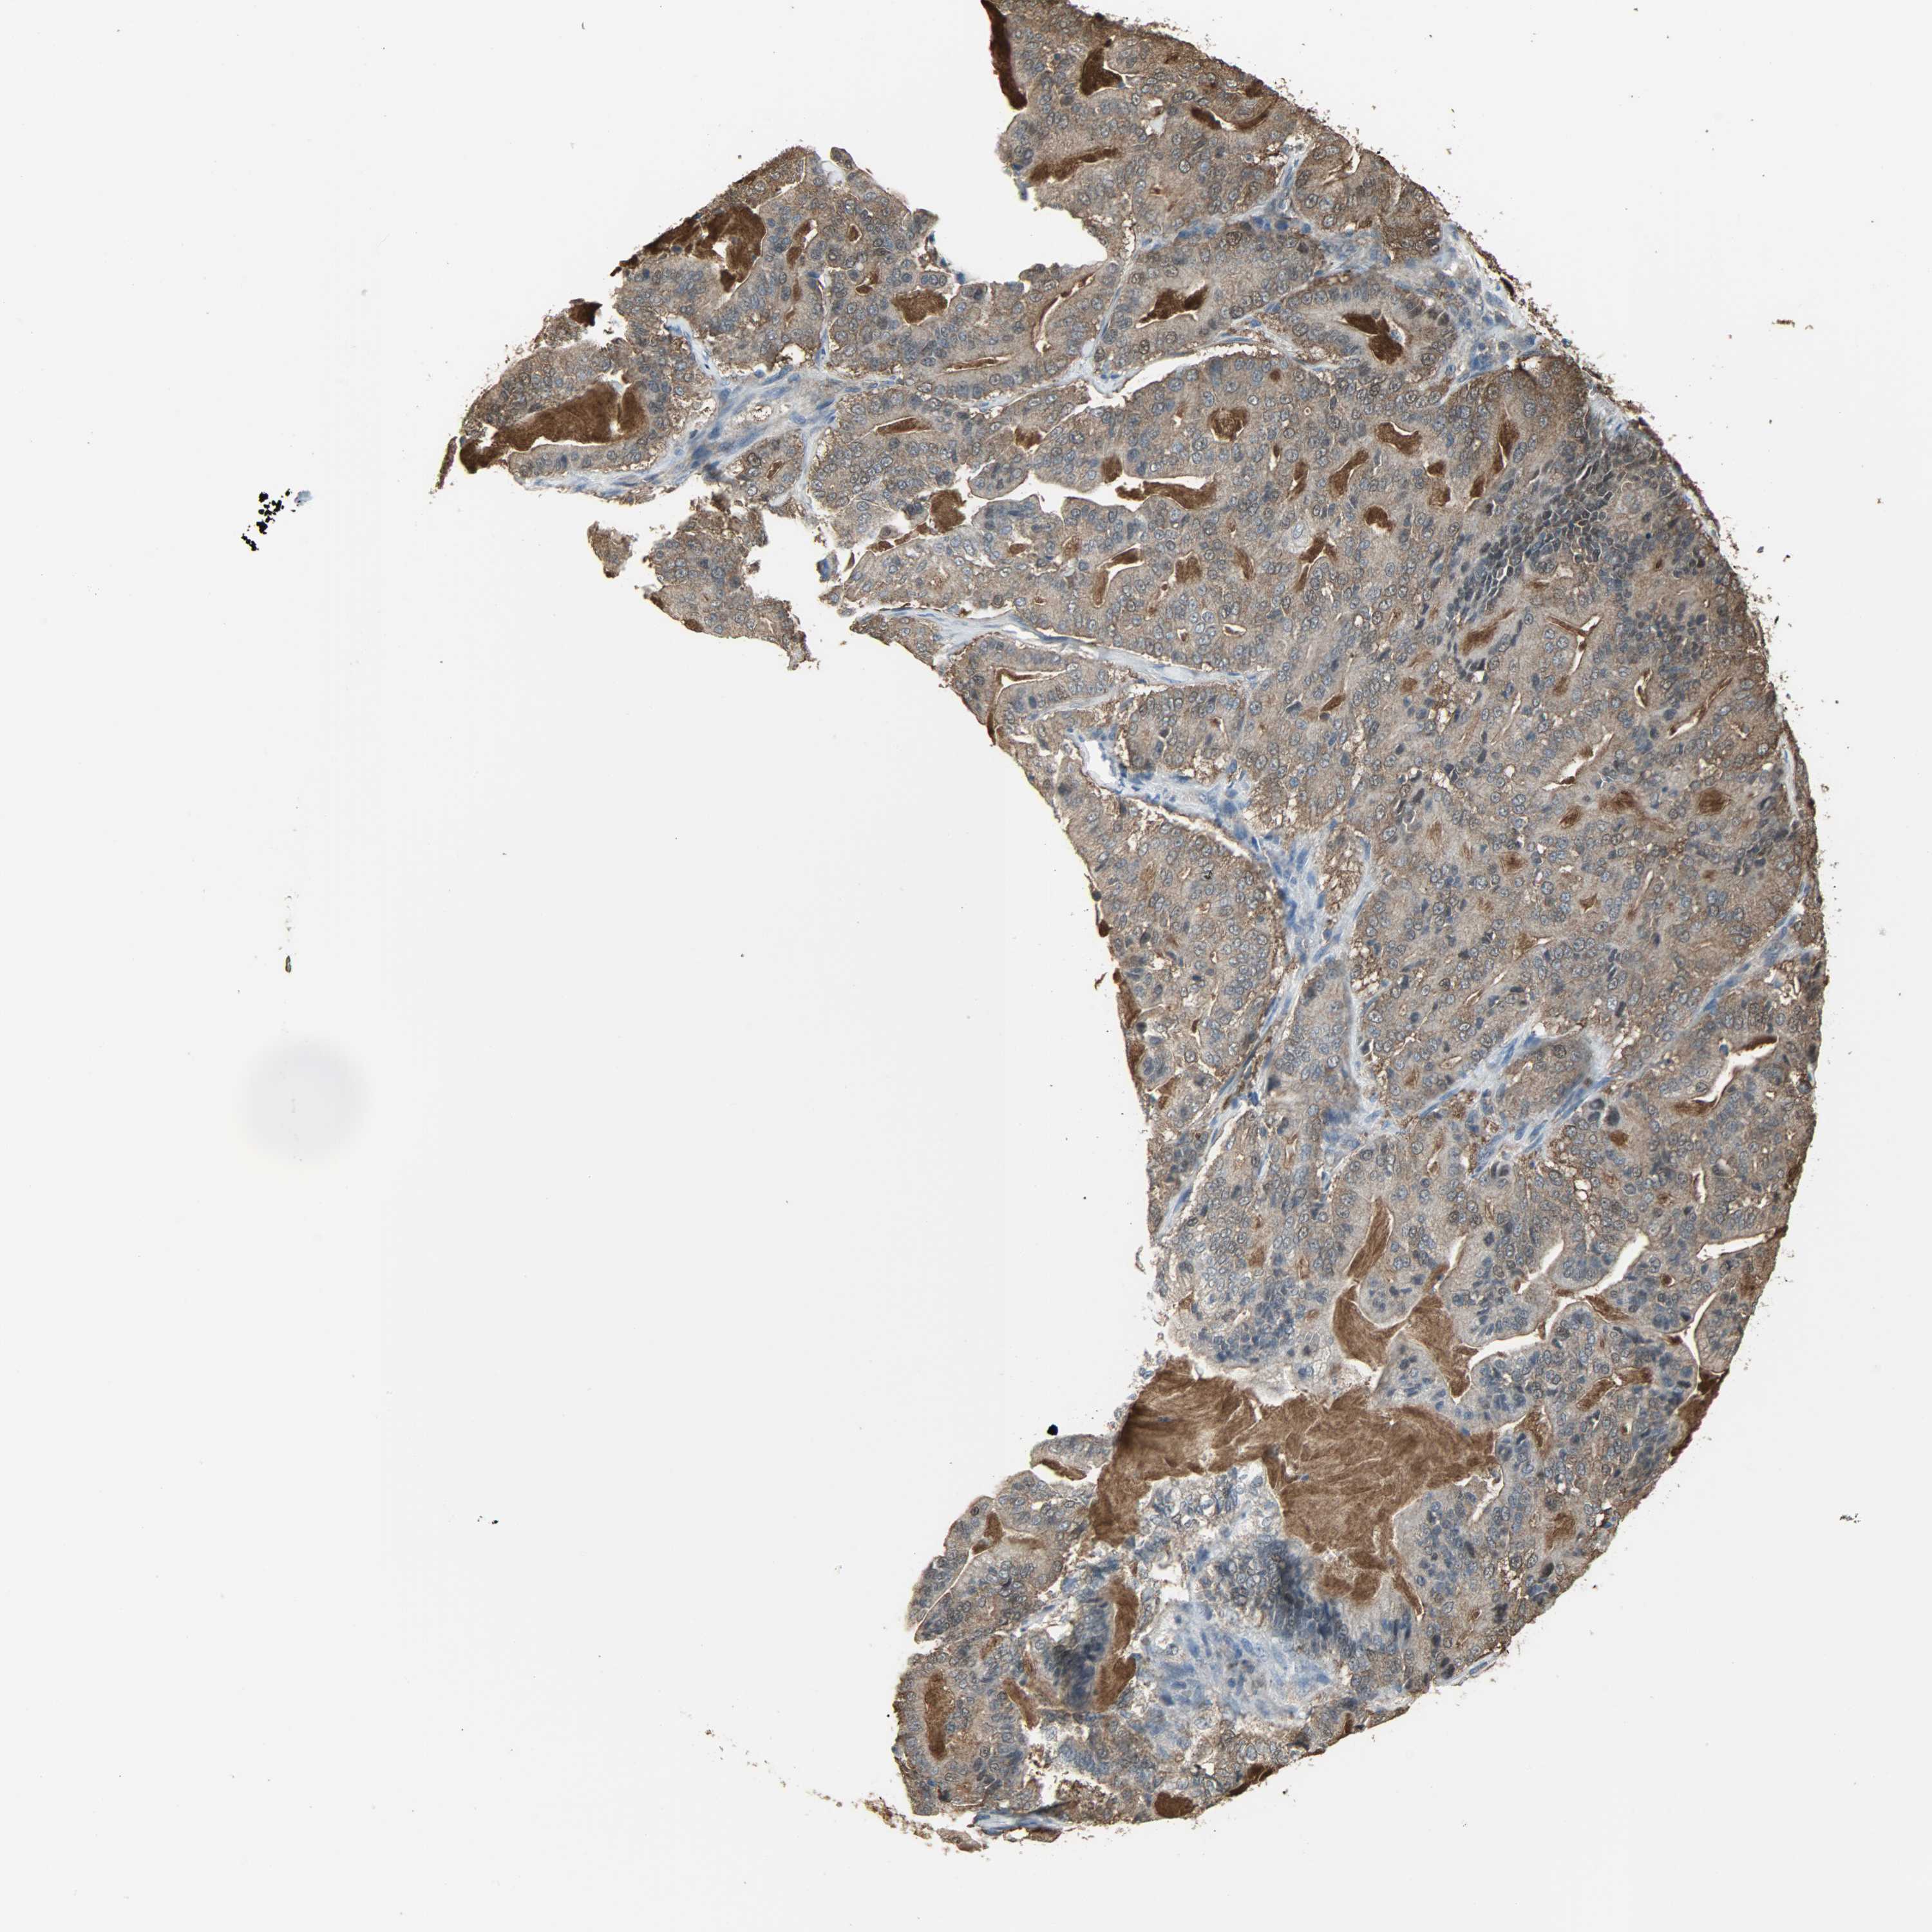

PANCREATIC CANCER - Protein expressioni

A mouse-over function shows sample information and annotation data. Click on an image to view it in a full screen mode. Samples can be filtered based on level of antibody staining by selecting one or several of the following categories: high, medium, low and not detected. The assay and annotation is described here.

Note that samples used for immunohistochemistry by the Human Protein Atlas do not correspond to samples in the TCGA dataset.

Antibody stainingi

Antibody staining in the annotated cell types in the current human tissue is reported as not detected, low, medium, or high, based on conventional immunohistochemistry profiling in selected tissues. This score is based on the combination of the staining intensity and fraction of stained cells.

Each image is clickable and will lead to virtual microscopy that enables deeper exploration of all samples and also displays staining intensity scores, fraction scores and subcellular localization as well as patient and tissue information for each sample.

Antibody HPA019007

Antibody CAB004641

Staining

High

Medium

Low

Not detected

Intensity

Strong

Moderate

Weak

Negative

Quantity

>75%

75%-25%

<25%

None

Location

Nuclear

Cytoplasmic/membranous

Cytoplasmic/membranous,nuclear

Adenocarcinoma, NOS

Adenocarcinoma, metastatic, NOS